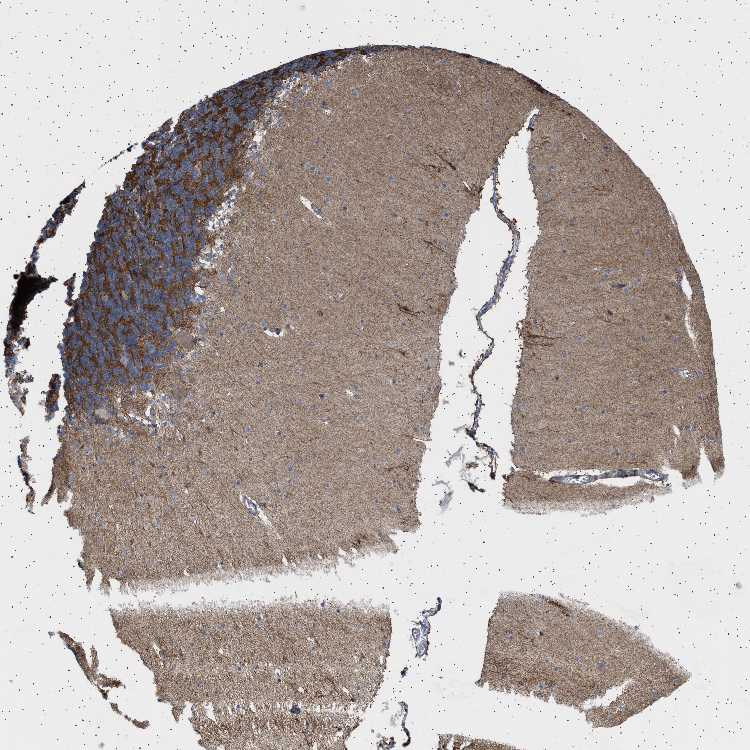

CEREBELLUM - Antibody stainingi

Antibody staining in the annotated cell types in the current human tissue is reported as not detected, low, medium, or high, based on conventional immunohistochemistry profiling in selected tissues. This score is based on the combination of the staining intensity and fraction of stained cells.

Each image is clickable and will lead to virtual microscopy that enables deeper exploration of all samples and also displays staining intensity scores, fraction scores and subcellular localization as well as patient and tissue information for each sample.

Antibody HPA018073

Purkinje cells Not detected

Cells in granular layer High

Cells in molecular layer Low